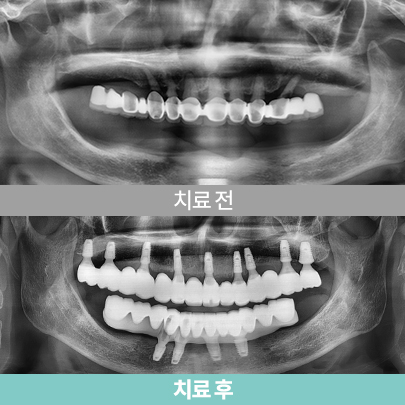

전악 임플란트

치아가 하나도 없거나 심각한 구강질환을 앓고 있어도

전악 보철을 제작, 임플란트를 치조골에 식립해

기능적, 심미적으로 자연치아와 가장 유사한 수준으로 재현이 가능합니다.